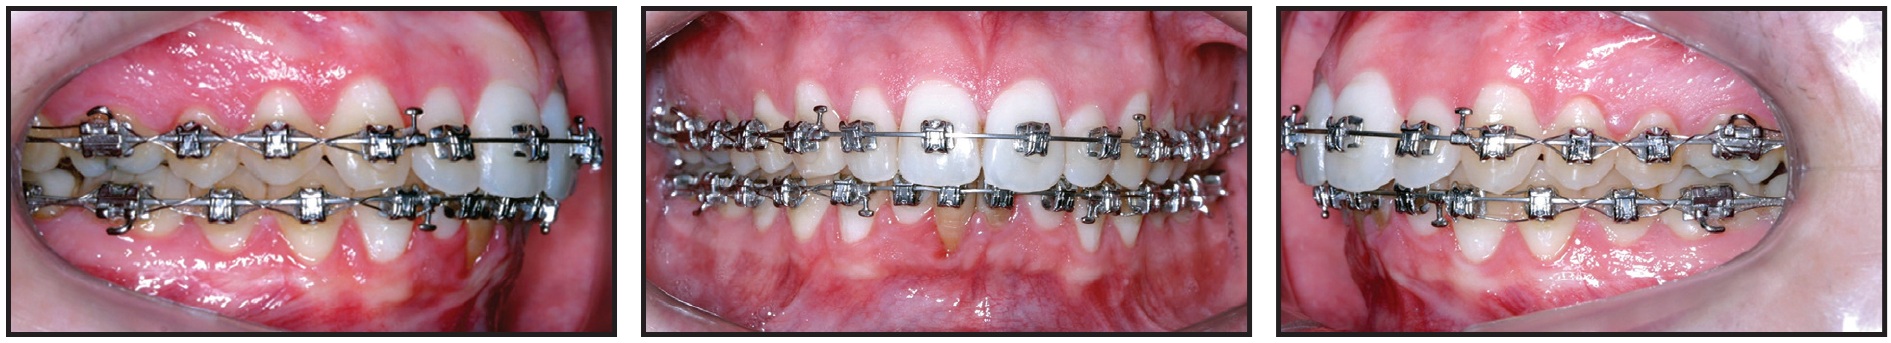

The lingually displaced lower right incisor was bonded after 23 months of treatment, when sufficient space had been opened for its traction and alignment. Torque control was then needed to align the roots of the lateral incisor buccally and the central incisor lingually. Because it is difficult to control torque on a round archwire, an inverted, U-shaped .017" × .017" TMA* segmental wire was inserted into the vertical bracket slots (Fig. 3). The .014" × .025" Copper NiTi archwire was inserted passively to control torque in all teeth until uprighting and alignment were complete.

Fig. 3 After 23 months of treatment, showing torque control of lower right central and lateral incisors with inverted, U-shaped .017" × .017" TMA** wire in vertical slots.

The .014" × .025" Copper NiTi archwire was inserted passively to control torque in all teeth until uprighting and alignment were complete.

In the Damon System, the patient’s archform is recorded with a wax bite registration at this stage, allowing for complete expression of the perioral musculature and the alveolar bone remodeling that occurs after arch expansion.9 The system then provides further expansion in the canine, premolar, and molar regions. In this case, the diagrammed .017" × .025" TMA archwires were inserted after 28 months of treatment for additional torque control and arch preparation. Finishing .019" × .025" TMA archwires were used for the last month (Fig. 4).

Fig. 4 After 34 months of treatment, showing .019" × .025" TMA finishing archwires.